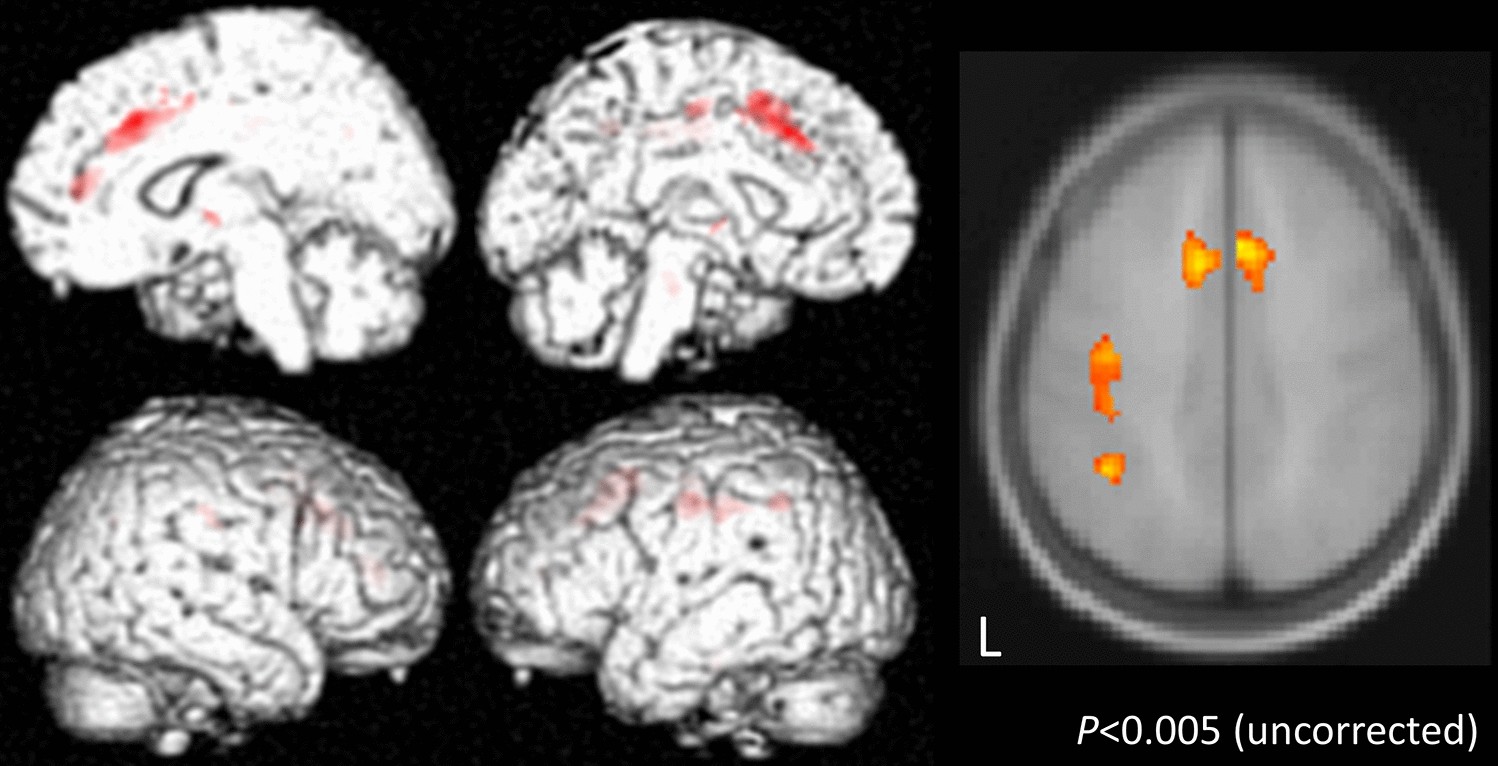

Figure 2

Voxel-based morphometry (VBM) comparing the CBS and PD groups. VBM analysis was performed on PD and CBS patients who had symptoms on the right side. The following area volumes were significantly decreased in the CBS group compared to the PD group: the left postcentral gyrus and precentral gyrus, and both sides of the supplementary motor area.